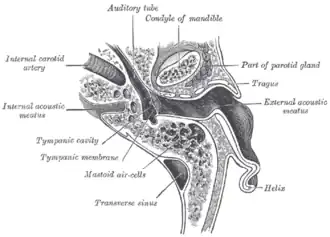

Horizontal section through left ear; upper half of section.

Horizontal section through left ear; upper half of section. -